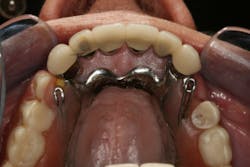

This clinical case began with a frustrated 75-year-old patient, who, after many years of failed attempts to repair the functional problem, came to the realization that a different solution was in order. The existing problem of an upper removable precision attachment partial denture was addressed first. The issue at hand was that the partial denture was perforated at the precision attachments, with the upper left side being more significant compared to the right side (figures 1–5). As a result, retention was adequate on the right side, but limited on the left. The patient was also concerned about esthetics, but needed a solution that kept a restricted budget in mind.

Occlusion: Localized wear noted on the lower anterior teeth, especially on teeth Nos. 22 and 23. Upper and lower planes of occlusion are not compatible for ideal function and esthetics.

Dentition: Upper anterior splinted crowns had open margins and caries. Radiographs confirm decay, along with open margins (figures 6–11). Lower incisal anterior wear noted (figure 2).

In this case, the diagnostic wax-up of the mounted models gave the technician the new position of the upper incisal edge. The technician then set the maxillary teeth appropriately using models and additional photographs. At the same time, tooth No. 20 was restored, but the lab technician kept the crown and lower partial to predictably create the lower occlusal plane and easily articulate this with the upper immediate denture (figure 18). Note the improved curve of Spee in Figures 19 and 20. Upon completion of the prosthesis, treatment was completed as outlined and the results made the patient feel very comfortable functionally, esthetically, and phonetically.